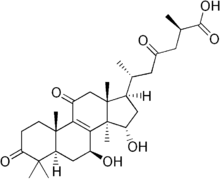

Ganoderma sichuanense is the most widely found species in Chinese herb shops today, and the fruiting bodies are widely cultivated in China and shipped to many other countries. About 7–10 other Ganoderma species are also sold in some shops, but have different Chinese and Latin names, and are considered different in their activity and functions. The differences are based on concentrations of triterpenes such as ganoderic acid and its derivatives, which vary widely among species. Research on the genus is ongoing, but a number of recent phylogenetic analyses have been published in the last number of years.[12]

Ganoderma lucidum contains diverse phytochemicals, including triterpenes (ganoderic acids), which have a molecular structure similar to that of steroid hormones.[48] It also contains phytochemicals found in fungal materials, including polysaccharides (such as beta-glucan), coumarin,[49] mannitol, and alkaloids.[48] Sterols isolated from the mushroom include ganoderol, ganoderenic acid, ganoderiol, ganodermanontriol, lucidadiol, and ganodermadiol.[48]